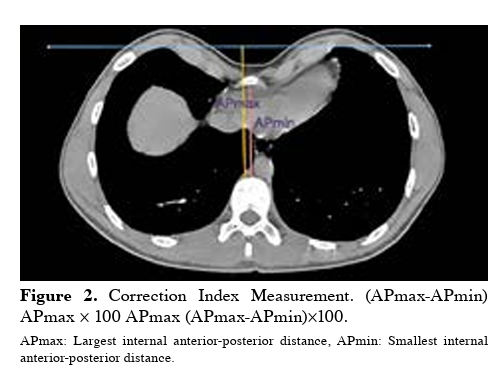

2. Correction Index (CI); Alternatif ölçüm, Daha hassas olabilir

3. Sternum elevasyonu; AP çap artışı, Göğüs duvarı normalizasyonu